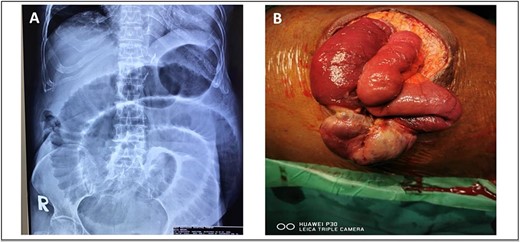

A 52-year-old Malay man, an active smoker, with underlying pulmonary hypertension secondary to atrial septal defect secundum with Eisenmenger syndrome and chronic lung disease. He had been experiencing symptoms of intestinal obstruction for a week. He had abdominal pain for 1 day, vomiting for 2 days, and unable to pass motion for the past 1 week. Patient was tachypnoeic with a respiratory rate of 35/min, a pulse rate of 116 bpm, and SPO2 of 90% under high-flow nasal cannula 50%/50 L. Abdominal radiograph showed dilated large bowel. Computed tomography abdomen and pelvis revealed short segment circumferential enhancing bowel wall thickening at rectosigmoid region causing intraluminal obstruction and presence of target sign at left lumbar region suggestive of jejunojejunal intussusception (Figs 2 and 3).

(A) Axial view and (B) sagittal view of computed tomography showed short segment circumferential enhancing bowel wall thickening at rectosigmoid region causing intraluminal obstruction (red arrow).